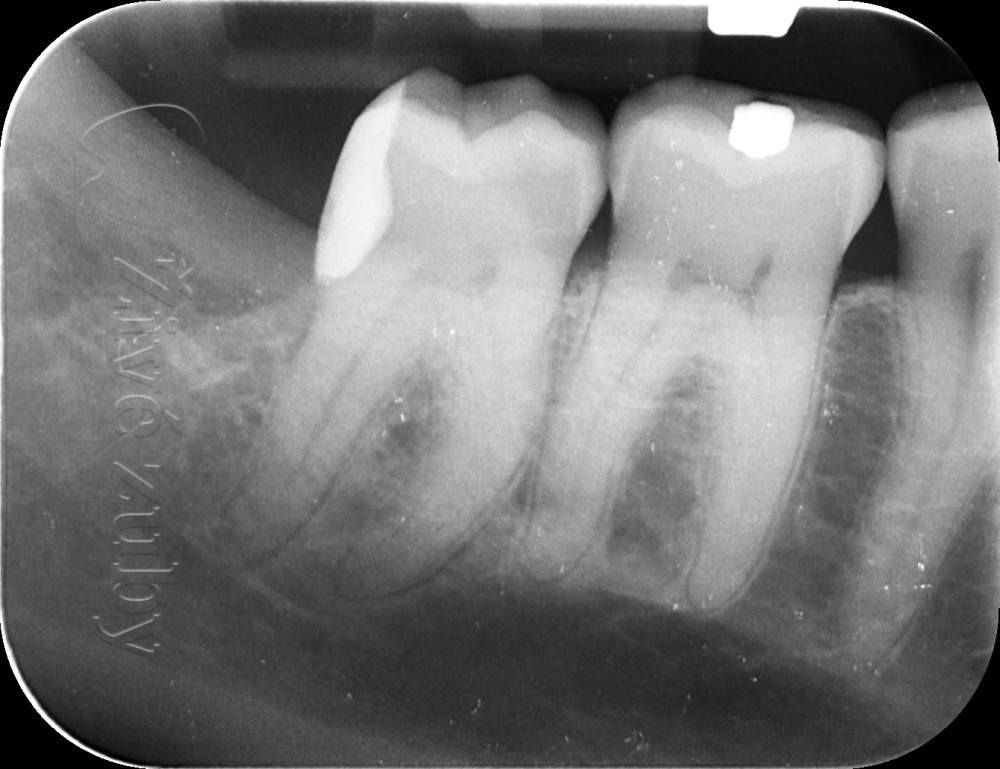

Ošetření hlubokých kazů

Výchozí stav  ——-> Kontrola po 2 letech ——--> Kontrola po 3 letech